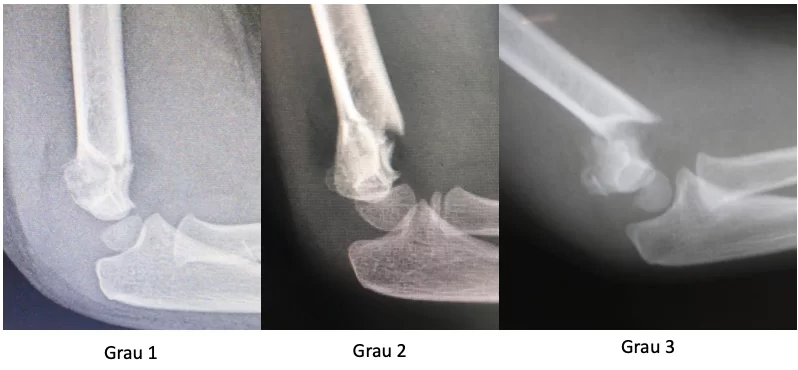

É necessário realizar uma radiografia em 2 posições (frente e perfil) para avaliar o desvio da fratura. Podemos classificar essa fratura em 4 tipos, de acordo com Gartland:

- Grau 1: Há uma fratura, porém ela é sem desvio,

- Grau 2: Há uma fratura, porém ela apresenta desvio para posterior. A cortical posterior está íntegra.

- Grau 3: Há uma fratura e ela está totalmente desviada. Tratamento cirúrgico.